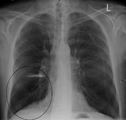

قد يفيد تصوير الصدر بالأشعة السينية والعد الدموي الشامل في استبعاد أسباب أخرى في وقت التشخيص.[52] والسمات المميزة للأشعة السينية هي التمدد الشديد للرئتين، وانبساط الحجاب الحاجز، وزيادة حيز الهواء خلف القص، والأمراض الجلدية، في حين أنها قد تساعد في استبعاد أمراض الرئة الأخرى مثل ذات الرئة ووذمة الرئة أو الاسترواح الصدري.[53] يمكن لصورة الصدر عالية الوضوح باستخدام التصوير المقطعي المحوسب بالأشعة السينية أن تبين توزيع النفاخ الرئوي في جميع أنحاء الرئتين ويمكن أيضاً أن تكون مفيدة في استبعاد أمراض الرئة الأخرى.[11] إذا لم يكن مخططاً لإجراء عملية جراحية، فهذا نادراً ما يؤثر على العلاج.[11] ويتم استخدام غازات الدم الشرياني لتحديد مدى الحاجة إلى الأكسجين؛ ويوصى به لمن يُتوقع أن يكون حجم الزفير القسري لديهم1 أقل من 35%، والذين لديهم تشبع أكسجين محيطي أقل من 92% والذين تظهر لديهم أعراض قصور القلب الاحتقاني.[10] في مناطق العالم التي يشيع فيها نقص مضاد التريبسين ألفا-1، يجب أن يوضع في الاعتبار اختبار الأشخاص المصابين بمرض الانسداد الرئوي المزمن (خاصة من هم دون سن 45 ولديهم نفاخ رئوي يؤثر على الأجزاء السفلية من الرئتين).[10]

صورة الأشعة السينية تبين حالة شديدة من الانسداد الرئوي المزمن. لاحظ صغر حجم القلب مقارنة بالرئتين.